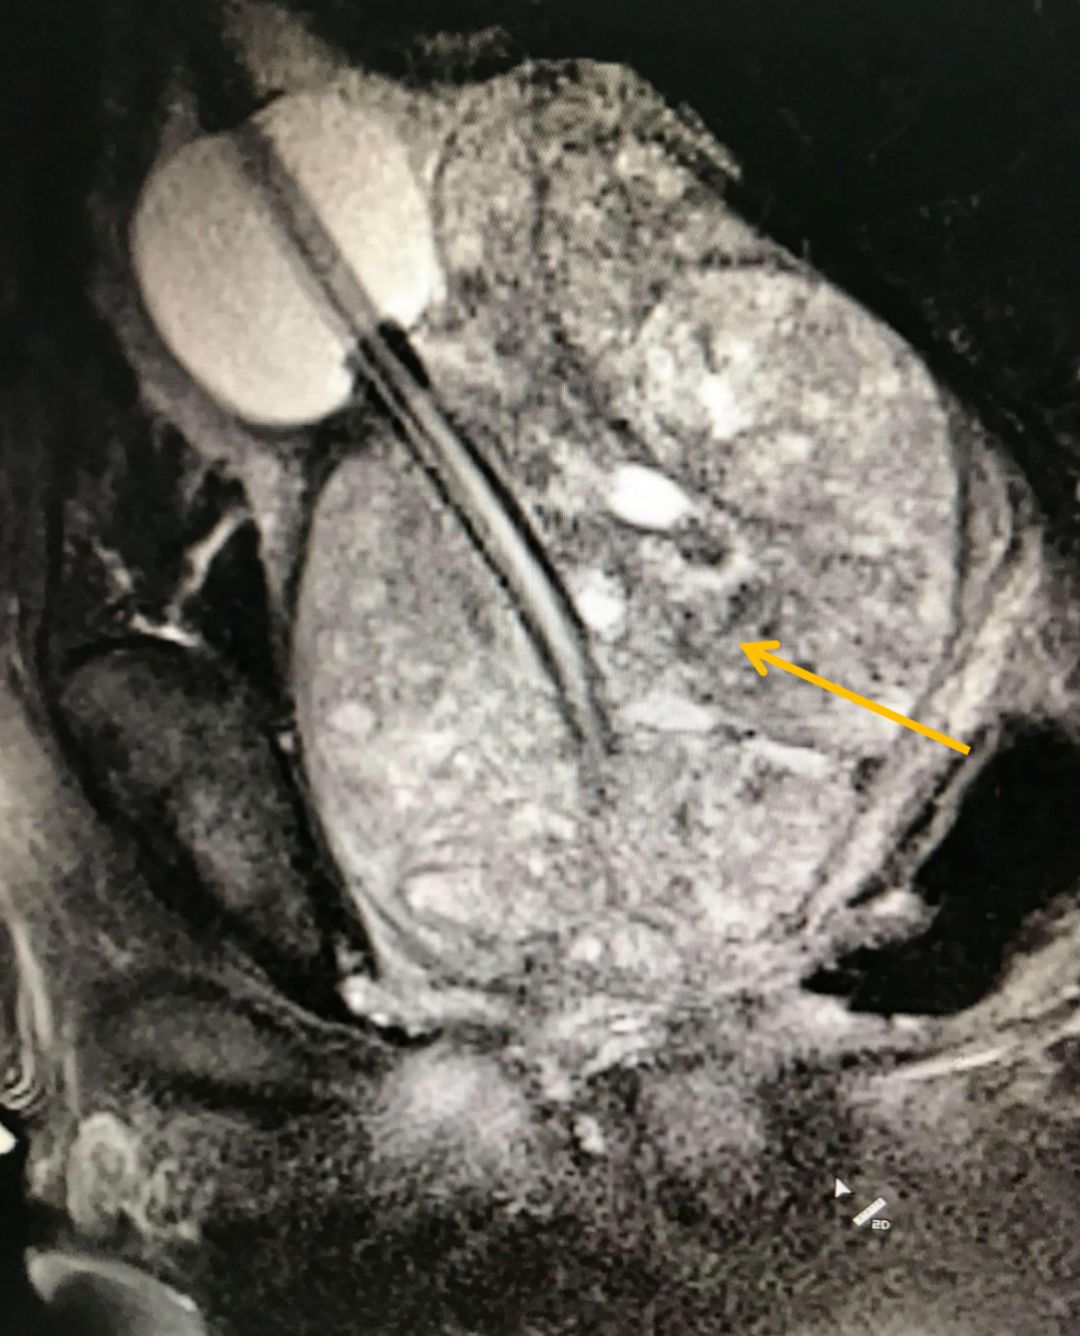

下面這張影像,展示的是一位重度前列腺增生患者的腺體——它如同一個巨大的核桃,緊緊扼住了尿道的“咽喉”。看到這樣的影像,我們對于他能否恢復順暢排尿,還能抱有多少期待?

圖:增生的前列腺(箭頭所指)擠壓尿道,導致排尿困難